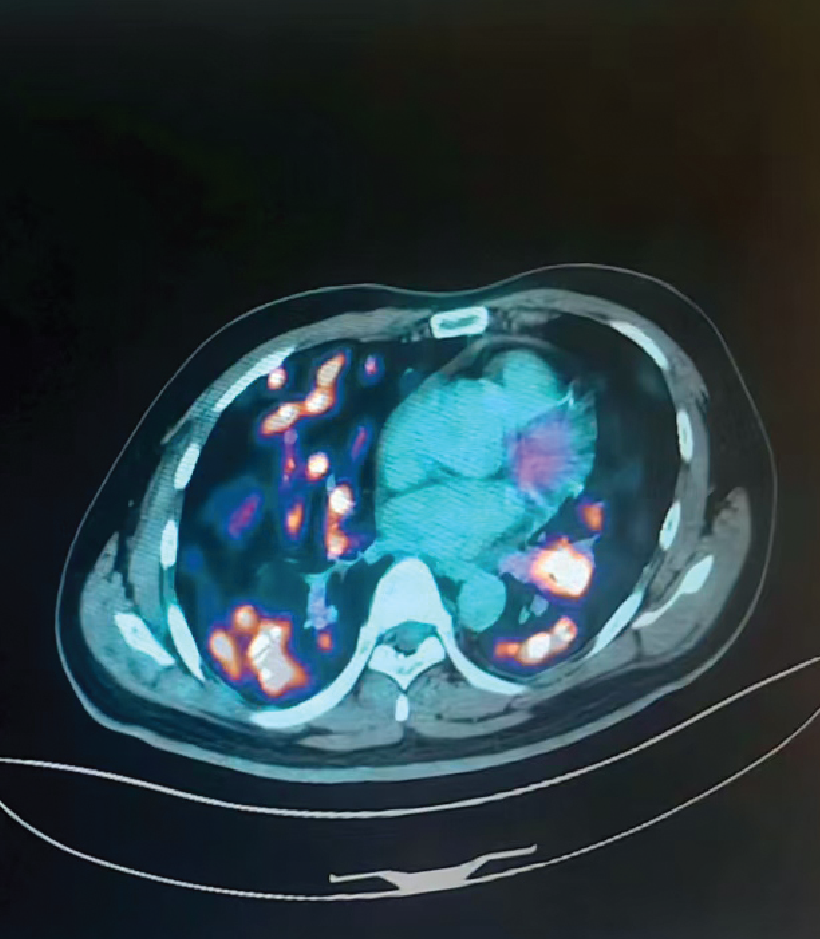

Before Treatment (Lung)

2-Month Follow-Up